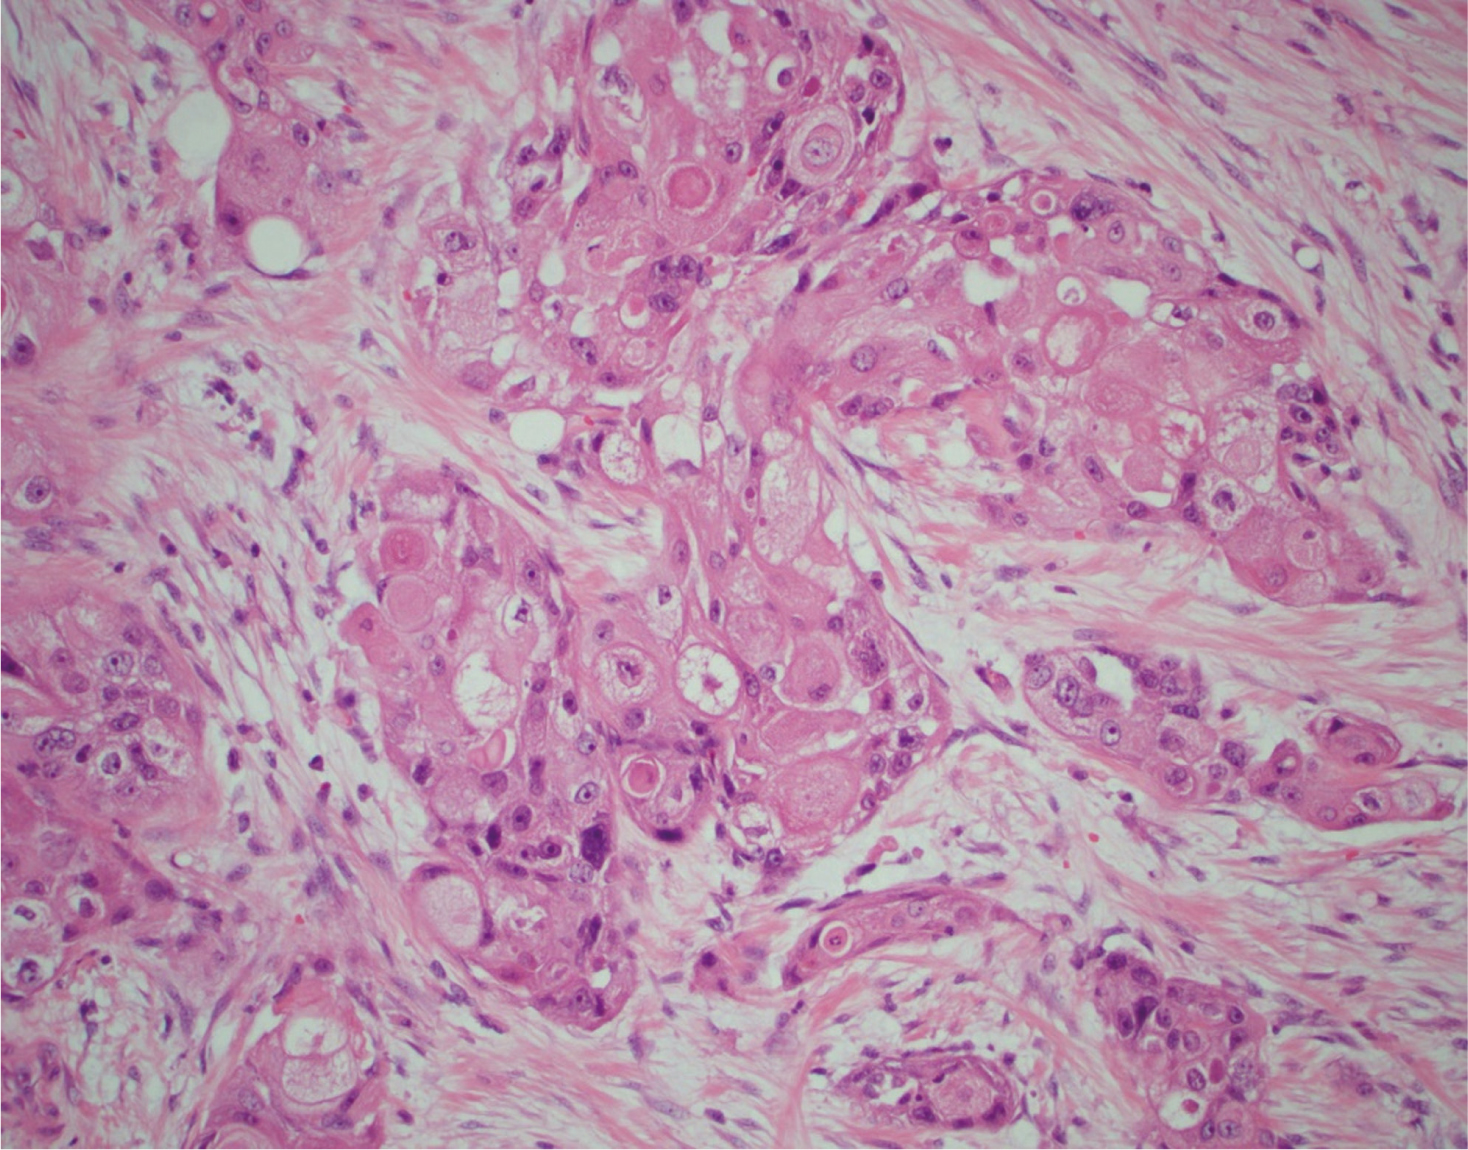

Macroscopic features showed a 45 mm cream-coloured tumour in the mid- to upper pole with no haemorrhage or necrosis (Figure 2). The tumour showed invasion through the IVC wall, extending into the psoas muscle. Histopathology demonstrated a moderately differentiated SCC with associated fibrosis (Figure 3). The tumour also showed extensive lymphovascular invasion and peri-neural invasion involving the vascular margin. Two of the five resected hilar lymph nodes demonstrated involvement, whereas the one resected pre-aortic lymph node did not demonstrate involvement. The patient was referred to a radiation oncologist to discuss the possibility of adjuvant radiotherapy.

Fig 3

Figure 3. Histopathology from tumour specimen demonstrating a moderately differentiated squamous cell carcinoma with associated fibrosis H&E × 200.